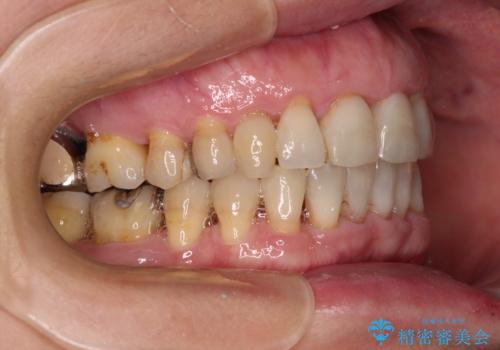

- 近医にてインプラント治療を行った後に矯正治療を希望され、来院された患者様です。

口元の突出感とデコボコが気になっているとのことでしたが、インプラントが既に3本埋入されていたため、抜歯矯正による口元を引っ込めることができない状況でした。

近医での歯周病治療の影響でブラックトライアングルが発現していたため、IPR(歯と歯の間を削る)で隙間を改善しつつ、インプラントを固定源に歯列全体を後方へ移動させることとしました。